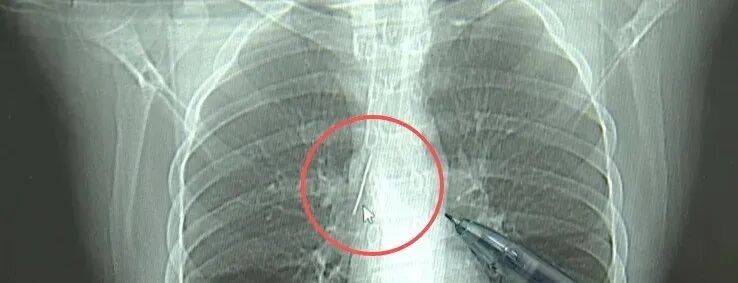

近日,安徽17岁小伙小陆参加征兵体检,胸片结果显示:胸腔内有一处金属高密度影,形态细长,像一根针。

进一步的CT检查确认,异物是一枚金属针,斜插在肺组织内,位置十分凶险。

杭州市第一人民医院心胸外科副主任冯兴说:“我们看到这个针的尖锐部,正好指向他体内的一个大血管,边上是上腔静脉和胸主动脉,因此这个针稍有不慎,就有可能造成周边血管的损伤,甚至危及生命。”